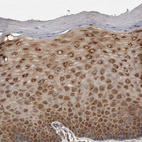

Immunohistochemical staining of human duodenum shows strong cytoplasmic positivity in lymphoid cells.